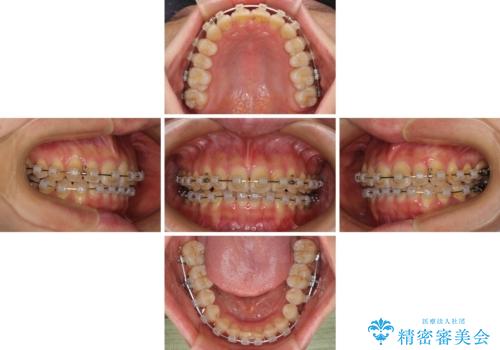

- クリアブラケット

- 治療期間

- 1年

- 上下前歯のデコボコを気にして来院された患者様です。

叢生は軽度で、ワイヤー矯正でもマウスピース矯正でも対応可能な歯列でした。

仕事と小さいお子さんの育児に追われており、インビザラインの自己管理は続ける自信がないとのことで、ワイヤー装置による矯正治療を行うこととしました。